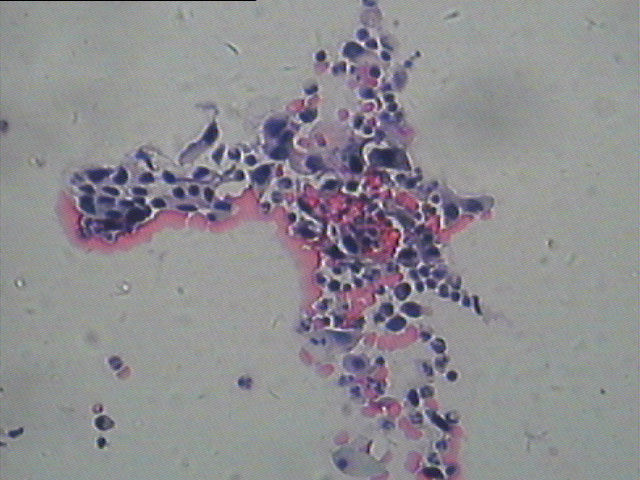

56岁,出血。离心法做的的,大家看 该怎么报

这个怎么报合适?求指导 求各种

鳞癌

hsil 如果不把握就asc-h 反正都是要活检

ASC-H,活检进一步明确诊断

鳞癌可能大。

hsil 可疑鳞癌,建议活检

HSIL    不除外鳞癌 建议活检

SCC